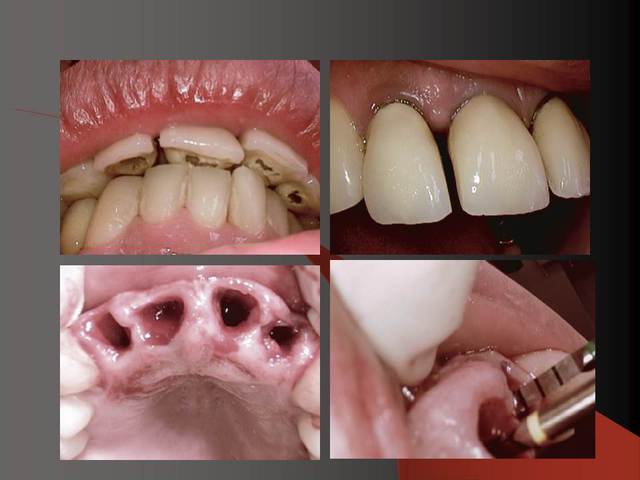

J´ai mis des photos pour mieux voir....

Sur la photo 5 on voit que je prépare surtout le titane de l´implant, le titane ne donne pas beaucoup du chaud quand il est préparé avec l´eau (pas comme aluminium par exemple).

je vais ajouter des autres photos ( c´est mieux pour moi de expliquer avec des photos... :-))